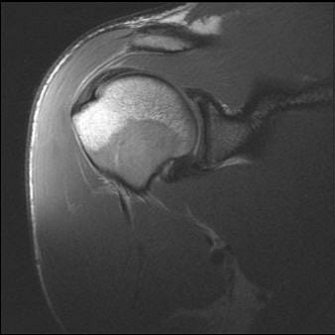

![]() |

| MR from same player as above. Oblique coronal proton-density-weighted images of the right and left shoulders show the massive bilateral muscle development. |